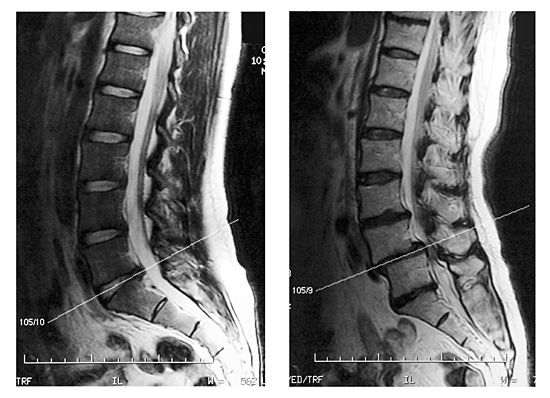

押圧法でいう“診断即治療”は筋性防衛を解除した後の触診により、圧加減を行ないます。さらに、常に自支姿勢を保ちますのであらゆる場面で危険回避は可能です。しかし、より多くの患者情報は治療期間の短縮や施術による危険回避の全てにおいて有益です。特にMRI画像は指圧治療に直接結びつく有益な情報を提供してくれます。詳細は講義で説明いたしますが指圧師の立場からMRI画像情報を解析する独自の知識や判断力も重要です。掲載したMRI画像は椎間板ヘルニアと脊柱分離症のMRI画像です。これらの画像診断以外に指圧師として重要な情報を多く含んでいます。判断がしやすいように画像処理を行ないました。左右のMRI画像を比較し、各自で一考してください。